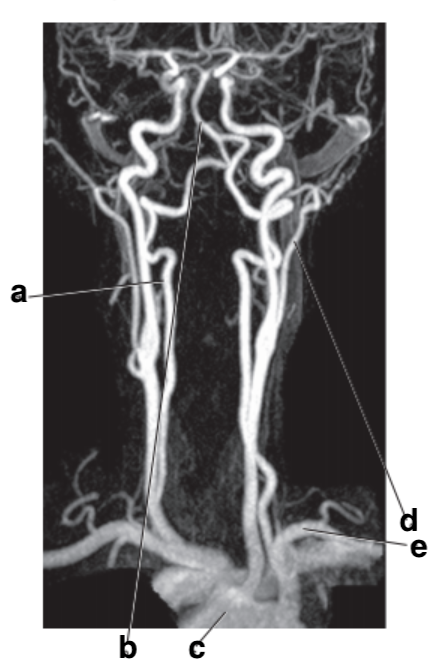

What is letter e?

Subclavian artery

Which letter is the popliteal artery?

A

Which letter is the left common carotid?

What is letter d?

Internal carotid artery

Number 2 is on the __________ side of the patient.

lateral

left popliteal artery